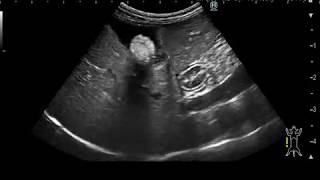

病院で胆石があるといわれ、そのまま入院となった。大きな石が2個エコー検査で写っている。胆嚢を摘出するのが完治になるそうだが、この時は胆のう炎を起こしているため、脇腹から炎症を起こしている胆汁を抜くことになった。この時は、石を残したまま、退院した。が、しかし、一か月も経たないうちに、再入院することになった。一週間ほど、熱があがったり、さがつたり、悪寒や嘔吐があったりしていたので、かかりつけの先生もこれは風邪ではなく、胆のう炎からきているということで前回の病院へ入院した。今回は、腹腔鏡下胆嚢摘出術で胆嚢ごと石も摘出した。